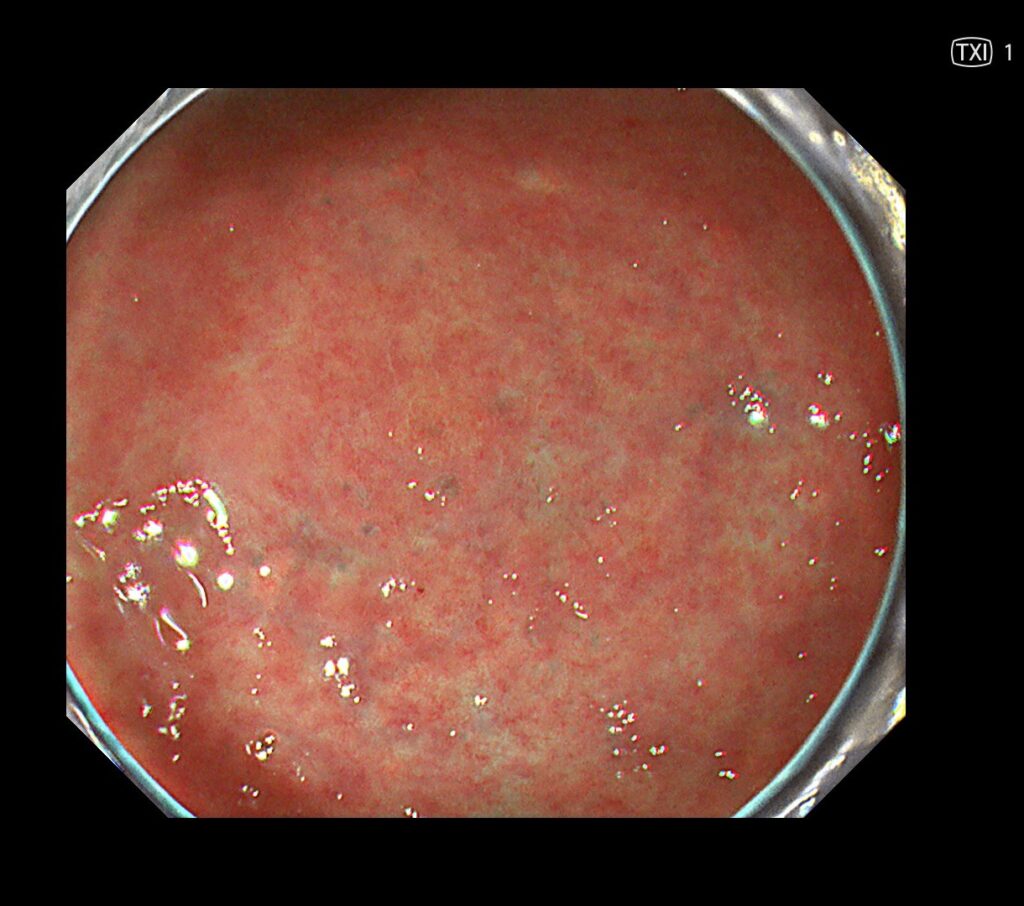

TXIモード(色と凹凸を強調するモード)にかえるとようやく、隠れていた胃癌が、画面中央に視認できるようになります。